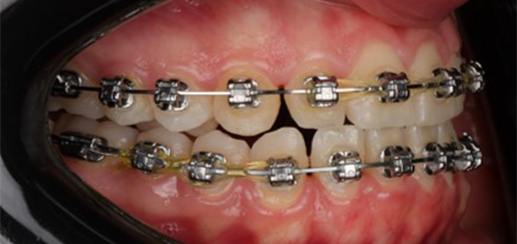

Initial leveling in the maxillary arch was carried out with a 0.014 CuNiTi archwire. This was followed by a 0.018 CuNiTi wire, with stoppers positioned mesial to the molars and activated to provide protrusion of incisors. The mandibular arch was then bonded and initial alignment was achieved with a 0.014 CuNiTi wire, then both jaws are progressing to 0.014 × 0.0275 CuNiTi and subsequently 0.018 × 0.0275 CuNiTi for torque control.

Finishing was completed with a 0.018 × 0.0275 TMA archwire in conjunction with Class III elastics.